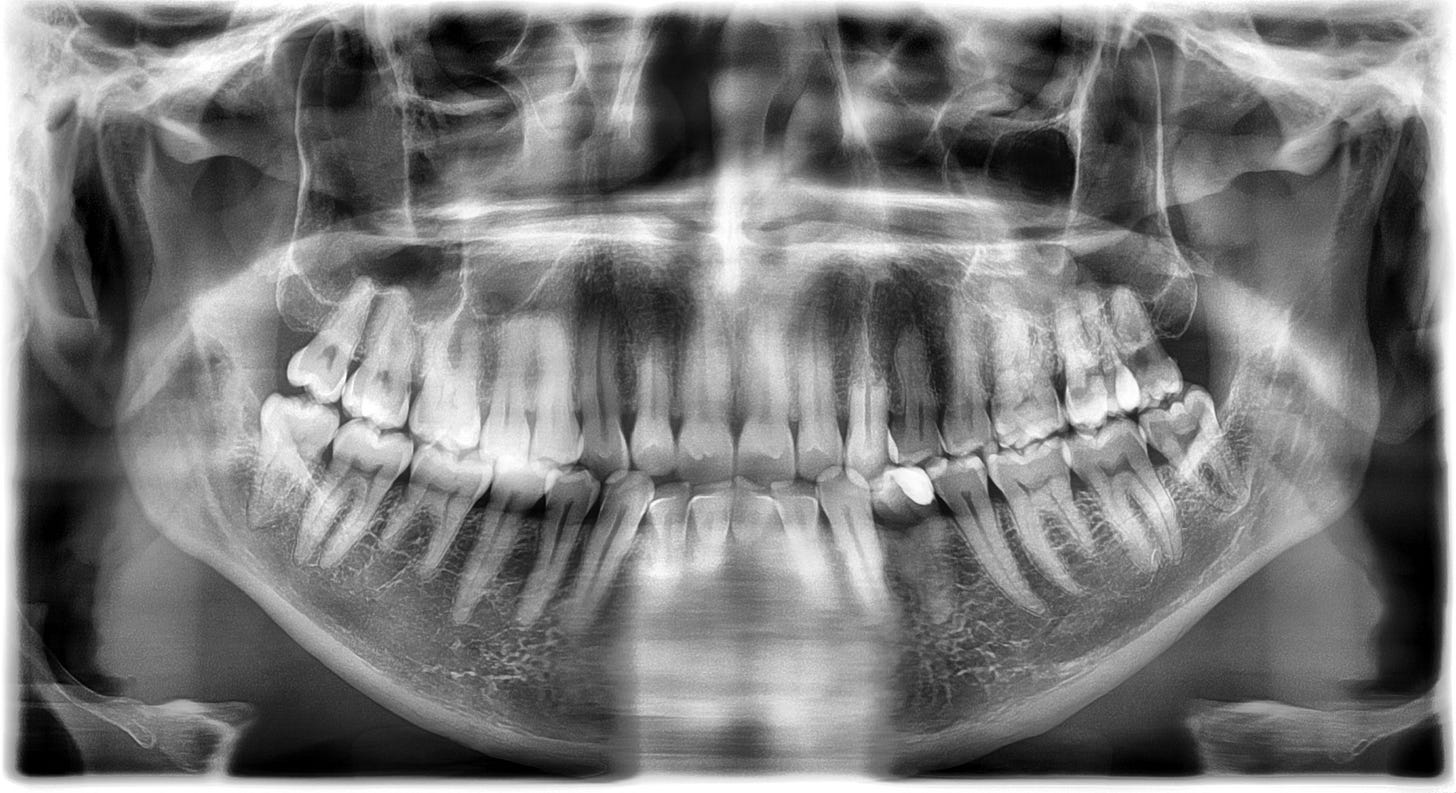

A panoral x-ray of my teeth from Dental 365 in Rotterdam.

My teeth started aching on our first day, after a post-travel nap. This continued as a dull ache throughout the left side of my jaw with intermittent prolonged, agonising sharp pain in one tooth (my first premolar on the left hand side: the one with the white filling visible in the x-ray. nb: the right side of the image is the left side of my face). When the sharp pain kicked in, after any change in my situation (hot, cold, moving, pausing, anything), I just had to stop and breathe until it eventually subsided.

Her diagnosis was that it wasn’t infected and was likely nerve damage from grinding my teeth. The fuzzy, indistinct image of the root implied that I’d been injuring that tooth for some time (something similar is happening on the upper teeth directly above it, which you can tell from the x-ray as my canines and premolars on the left have less distinct roots than those on my right, because the root is being resorbed. This is an ongoing issue for me, and I already have a mouthguard for it, so didn’t come as a surprise). She thought root canal surgery would solve the pain, which could have happened there and then, but suggested that I may prefer to have that done at home, which I agreed with. I left €130 lighter, with a prescription for hefty ibuprofen, and the knowledge that at least it wasn’t an infection that might turn septic.

Last Monday (3rd November), a painful week after my visit to the dentist in Rotterdam, I had an emergency appointment in Southampton, expecting to have root canal surgery. But, after a second set of x-rays that dentist told me the anatomy of the tooth was unusual, it may have three or four roots, and the nerves look as though they might be curved, so it wouldn’t be easy and may not solve the problem. I got a referral to an endodontist (a specialist on the inside of teeth) for a CT scan, which will happen this coming Monday, to try and understand what is going on in my mouth.